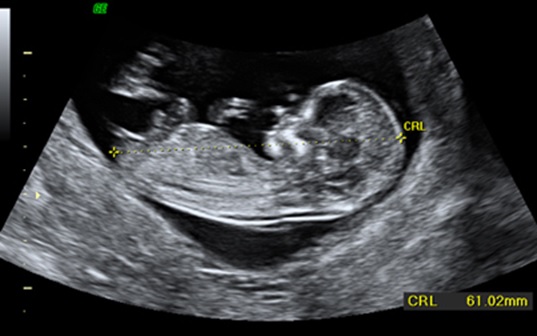

Pruebas, Citas y Ecografías

durante el Embarazo